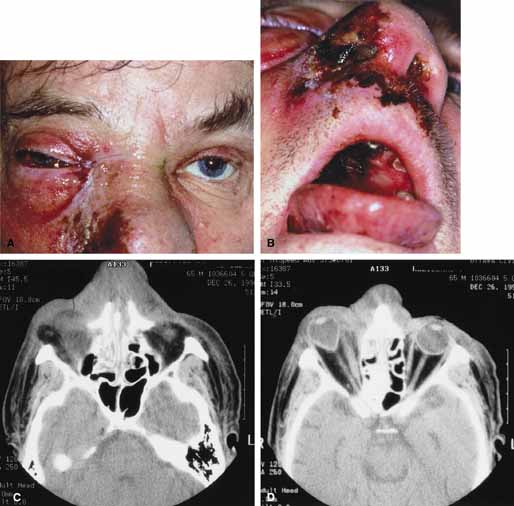

ORBITAL CELLULITIS Orbital cellulitis is the model for acute inflammation and a major cause of orbital inflammation in adults.2 It is characterized by a rapid development (over 1 to 2 days) of inflammatory signs and symptoms. These include: eyelid swelling, redness, warmth, pain, conjunctival injection, chemosis, proptosis, and mobility impairment with or without reduced vision. These patients generally feel unwell (malaise) and are febrile (Fig. 1A and 1B). The malaise and fever are key features in differentiating cellulitis from a rapid-onset nonspecific orbital inflammation (pseudotumor) and should be obtained from the patient's history. The majority of orbital cellulitis is secondary to extension from an adjacent sinus infection (Fig. 1C). Organisms gain access to the orbit directly through the thin ethmoidal bone, through congenital or acquired dehiscences in the thin orbital walls, pass through preexisting orbital foramina, pass retrogradely through the valveless venous orbital system, or along the veins as a periphlebitis. Orbital cellulitis may also be secondary to an endophthalmitis, systemic bacteremia (e.g., after dental work), infection of a nearby skin wound, dacryocystitis, or penetrating trauma. The history and physical examination are crucial in distinguishing between preseptal and true orbital cellulitis. The orbital septum delineates the anterior eyelid soft tissue from the orbital soft tissue. Infections anterior to the septum are classified as preseptal cellulitis while those posterior to the septum are termed orbital cellulitis. Recognition of true orbital involvement is important not only because of the threatened visual loss associated with the orbital involvement but also because of the potential for central nervous system complications including cavernous sinus thrombosis, meningitis, and death. Preseptal cellulitis is characterized by lid edema, erythma, and discomfort. Inflammation posterior to the orbital septum (orbital cellulitis) is heralded by the development of pain, chemosis, proptosis, motility disturbance, and visual deterioration. The extent of ocular involvement in preseptal and orbital cellulitis can be determined by assessing visual acuity, extraocular motility, pupillary reaction, color vision, confrontation visual fields, intraocular pressure, and optic nerve head appearance. Evidence of facial/head trauma or surgical wounds may be apparent. Constitutional signs such as fever, lethargy, and irritability should be sought. The examiner should assess for meningeal signs and neurologic defects. After the initial examination, the physician should follow patients with orbital cellulitis with at least daily assessments of visual acuity, motility, and pupil reaction. Progression of the disease process despite appropriate antibiotic therapy suggests abscess formation. Orbital abscesses may be either localized, diffuse, or subperiosteal (Fig. 1C). Subperiosteal abscesses most commonly occur along the medial wall and may expand rapidly, compromising optic nerve function even in the absence of many signs of infection.3–6 Several mechanisms may contribute to visual deterioration including direct optic nerve compression, elevation of the intraorbital pressure, and proptosis causing a “stretch” optic neuropathy. Clinically, the eye typically is displaced away from the subperiosteal abscess, and orbital imaging shows a convex mass adjacent to the involved sinus. Orbital infection with potential orbital abscess formation occurs when bacteria break through the periorbita and gain access to the extraoconal or intraconal space. Diffuse or localized orbital abscess formation may also lead to visual loss through an increase in intraorbital pressure, posterior ischemic optic neuropathy, optic nerve inflammation, or vasculitis. Acute visual loss in the presence of an orbital infection is almost always a surgical emergency in which immediate drainage of the abscess is required to save vision. Continued posterior extension of the infection may result in an orbital apex syndrome, decreased function of cranial nerves,2–6 thrombosis of the cavernous sinus, and even death. Hallmarks of cavernous sinus thrombosis include cranial neuropathy and central neurologic impairment.7 Organisms responsible for orbital cellulitis vary widely and may include Staphylococcous aureus, Streptococcus species, as well as a mixture of aerobes and anaerobic organisms. Recent studies indicate that streptococcus is the most common cause of orbital cellulitis associated with sinusitis in children.8 With increasing age the pathogens increase in complexity. In patients older than 15 with subperiosteal abscesses, polymicrobial infections are typical with anaerobes cultured in every case.5 Orbital imaging in the axial and coronal plane should be obtained in all patients suspected of having orbital cellulitis. Computed tomography (CT) is preferred to magnetic resonance imaging (MRI) because the orbital tissues have higher contrast and bone is well visualized. Axial CT views allow evaluation of the medial orbit and ethmoid sinuses, whereas coronal scans image the orbital roof, floor, frontal, and maxillary sinus. A subperiosteal abscess appears as a homogeneous opacification between the orbital wall and the displaced periorbita.6 Contrast agents are not necessary to visualize a subperiosteal abscess. Management of orbital cellulitis is dictated by the rapidity of onset. Oral antibiotics may be appropriate for mild cases whereas intravenous antibiotics are required for more fulminant cases. Antibiotic coverage should be broad spectrum and include coverage for gram-positive organisms and anaerobes. Examples include cloxicillan and clindamycin or a late-generation cephalosporin and clindamycin. In those patients allergic to penicillin agents, erythromycin and clindamycin or vancomycin and clindamycin are considerations. Most patients with orbital cellulitis also benefit from a nasal decongestant as well as an oral decongestant and warm compresses to the affected site (10 minutes out of every hour). Daily or more frequent reexaminations are required depending on the fulminancy of the disease. Once antibiotics are initiated, a 24-hour wait-and-watch period is generally observed (unless the process is aggressive and rapidly developing). If there is no progression at 24 hours and the vision is stable, continued observation is appropriate. If the orbital cellulitis is rapidly developing and fulminant, frequent assessments (every 2 to 4 hours) are required. If the vision, motility, or neurologic status is deteriorating, immediate surgical intervention may be required. The indication for surgery in a patient with orbital cellulitis has been controversial over the years. The simple presence of a subperiosteal abscess (SPA) was at one time an indication to drain but this is no longer always the case. Providing the vision is normal, the SPA may resolve with medical management. The clinical course, and not the radiographic appearance should dictate management.5,6,9 Surgical therapy may be influenced by many factors including the visual status, size, and location of the SPA; intracranial complications; the sinus involved; the presumed pathogenesis, and the anticipated bacterial response to antibiotic treatment.10 Immediate drainage of SPAs and sinuses is recommended for patients of any age whose vision is compromised. Urgent drainage (as soon as practical) should be considered for large SPAs, extensive superior or inferior abscesses, intracranial complications at the time of presentation, frontal sinusitis where the risk of intracranial extension is increased, and in those suspected of having anaerobes (postdental procedures). However, cookbook approaches should never take the place of good clinical judgement and therapeutic decisions regarding early drainage versus medical management with observation are ultimately up to the managing physician.10 Older children (older than 9 years of age) and adults benefit from early surgical drainage. Although surgical treatment does not guarantee rapid resolution, a complicated course is more likely without it.10 Abscesses may also develop within the intraconal space. The prescence of an abscess within the orbital tissue coupled with any signs of visual loss, afferent pupillary defect, or a significant motility defect should prompt emergent surgery. If visual acuity is stable and extraocular motility essentially full, initial treatment may consist of empiric antibiotic therapy and close observation with serial CT scans. The prescence of neurologic symptoms such as altered mental status or seizures implies intracranial extension with potential intracranial abscess. Infection may spread from the sinuses to the intracranial cavity via retrograde thrombophlebitis, directly through osteitic bone or from congenital or acquired bony defects. In the past, intracranial abscess formation had a poor prognosis with a high mortality rate. Successful management of suppurative abscesses requires early recognition of the disease process, intravenous antibiotics, serial neuroimaging, and surgical management of at least the orbit and sinus disease and often the intracranial disease.11 PHYCOMYCOSIS (RHINO-ORBITAL MUCORMYCOSIS AND ORBITAL ASPERGILLOSIS) Rhino-orbital mucormycosis, a fungal infection of class Phycomycetes and order mucorales, is notable for its high morbidity and mortality.12,13 Orbital involvement is an acute, aggressive, and often lethal infection if not recognized early. Phycomycetes (common bread molds) are ubiquitous fungi occurring in soil, air, skin, body orifices, manure, and food including fruit.13 Inoculation occurs by inhalation reaching the nasopharynx and oropharynx. At this stage most patients are able to contain the disease. However, individuals whose cellular and humoral defense mechanisms have been compromised by disease or immunosuppressive treatment may not be able to generate an adequate response. The fungus may then spread to the paranasal sinus, orbit, meninges, and brain by direct extension.13 Mucormycosis preferentially involves blood vessel walls resulting in vascular occlusion, thrombosis, and infarction.14 This frequently affects the ophthalmic artery and in more serious cases may involve the internal carotid artery and cavernous sinus. Although there have been a few reports of mucormycosis occurring in healthy individuals, virtually all other patients have had previous severe underlying disease. The patient most vulnerable to this infection is an one with uncontrolled diabetes with ketoacidosis. A host of other conditions also predispose patients to the disease including: multiple myeloma, lymphoma, organ transplantation with immunosuppresion, chemotherapy, corticosteroid treatment, acquired immunodeficiency syndrome, etc.(Fig. 2A).12–14 Mortality is extremely high for patients with phycomycosis infection, and successful treatment is contingent on early recognition and prompt treatment. A characteristic pattern of clinical symptoms and signs occurs, the recognition of which should lead to the immediate institution of antifungal treatment and possible surgical intervention to increase the patient's chances of survival. Early diagnosis while the disease is still somewhat anatomically confined is essential for a more favorable outcome.12–14 Characteristic features of orbital mucormycosis include an immunocompromised patient with sinusitis, pharyngitis or nasal discharge who develops cellulitis of the face or lid. Signs and symptoms include orbital/periorbital pain, acute proptosis, abrupt visual loss, orbital apex syndrome with acute motility changes (external ophthalmoplegia), pupillary changes (internal ophthalmoplegia), ptosis, and decreased corneal sensation. Infarction of tissue results in black eschar formation of the skin, nasal mucosa and hard palate (Fig. 2A and 2B).12,13 With intracranial extension, the patient generally become obtunded, develops convulsions, contralateral hemianaesthesia or hemiplegia, and lapses into coma. CT scanning demonstrates an orbital mass often with bone destruction and sinus involvement (Fig. 2C and 2D). The diagnosis is confirmed by biopsy of involved tissue with demonstration of characteristic nonseptate, large, branching hyphae, which can be seen on routine hematoxylin and eosin stains. Material should be submitted for both frozen and conventional paraffin-embedded sections. Frozen sections are not always definitive and the surgeon must have considerable confidence in the skill of the pathologist. 13 Management includes: (1) early definitive diagnosis; (2) correction of any underlying metabolic disturbance; (3) wide local excision with debridement of all involved and devitalized oral, nasal, sinus and orbital tissue; (4) establishment of adequate sinus and orbital drainage; (5) daily irrigation and packing of the involved orbital and paranasal areas with amphotericin B; and (6) intravenous amphotericin B.12,13,15 The extent of surgical excision should balance the degree of morbidity and mutilation against the life-threatening risk this organism represents. In limited cases, surgical excision may be confined to those tissues clearly infarcted. Should infection be extensive as demonstrated by widespread necrosis, then aggressive surgery, including exenteration of the orbit and any involved paranasal sinuses, may prove necessary and lifesaving.13 ORBITAL ASPERGILLOSIS Aspergillus, a fungus of the Ascomycetes class, is a common environmental organism that may colonize the aerodigestive tract. Although widespread, the fungus has a low intrinsic virulence and clinically apparent aspergillosis is rare in the immunocompetant host. Invasive aspergillosis, similar to mucormycosis, occurs more often in the immunocompromised host, including patients undergoing transplantation or steroid therapy, neutropenic patients undergoing chemotherapy, alcoholics, patients with diabetes, and patients with acquired immune deficiency syndrome (AIDS).16–20 Orbital involvement may be slowly progressive or abrupt in onset with orbital inflammation, proptosis, pain, ophthalmoplegia, and sudden loss of vision.16,19 Fulminant aspergillus infection of the nose, paranasal sinus, and orbit often associated with intracranial extension has been reported with increasing frequency in immunocompromised individuals.17,18 In these patients, local invasion of the sinus mucoperiosteum produces a rapidly progressive gangrenous necrosis.18 With bone destruction, infection may extend into the orbit and intracranial cavity; the latter has a poor prognosis. The fungus may also spread by hematogenous routes.17 Imaging studies reveal sinus involvement, heterogenous soft tissue masses with bony erosion, and calcification.16 A definitive diagnosis of aspergillosis is based on tissue biopsy and fungal cultures. Treatment of invasive sino-orbital aspergillosis involves aggressive surgical debridement combined with a systemic antifungal agent. Intravenous amphoticin B has been the mainstay of medical therapy but toxic side effects, especially renal, require discontinuing the medication in some patients. Newer systemic antifungal agents include liposomal amphotericin B (fewer renal toxic effects) and oral intraconazole.21–24 Adjuvant local irrigation of amphotencin B has also been recommended.24 For patients unable or unwilling to undergo surgery, intralesional injection of amphotericin B has been used successfully as palliative treatment.25 Despite aggressive therapy, the mortality in those with invasive sino-orbital aspergillosis remains high.17 |